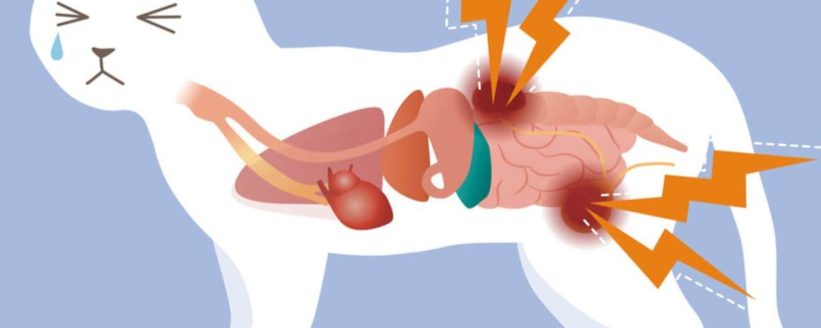

Kedilerde Böbrek Hastalıkları: Erken Teşhis ve Yönetim Rehberi

Kedilerde Böbrek Hastalıkları: Erken Teşhis ve Yönetim Rehberi Kedilerde böbrek hastalıkları, özellikle yaşlı kedilerde en yaygın ölümcül durumlardan biridir. Kronik böbrek yetmezliği, sinsi ilerler ve erken evrelerde belirti göstermez; bu nedenle düzenli veteriner kontrolleri ve erken teşhis hayati önem taşır. Bu rehberde, kedilerde böbrek hastalıklarının belirtilerini, teşhis yöntemlerini, tedavi seçeneklerini…